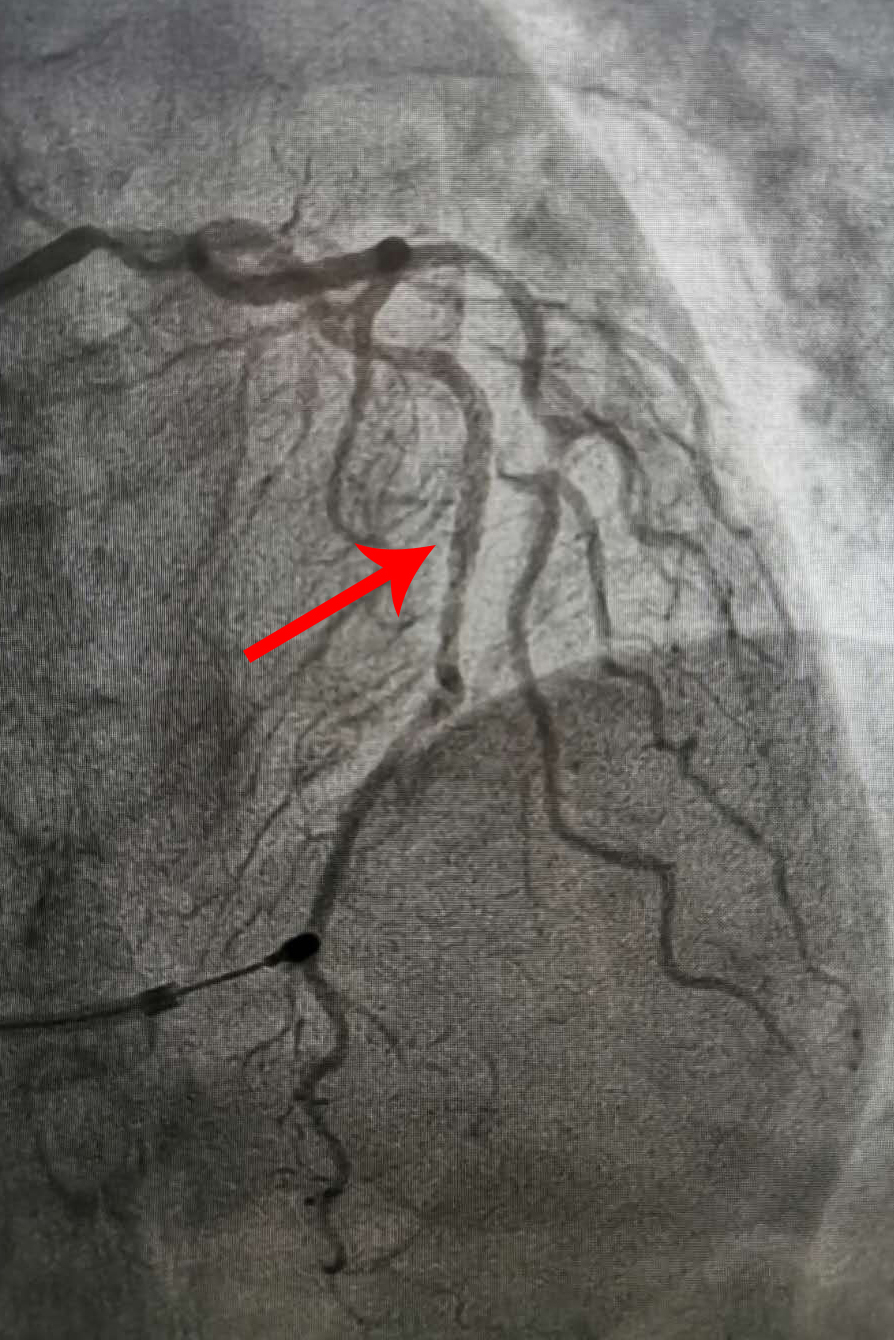

術前:冠脈動脈嚴重狹窄

冠脈支架植入后